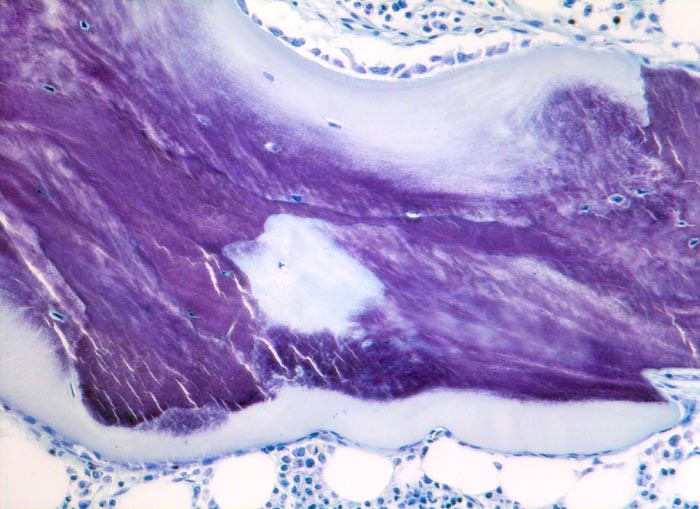

Osteoidose: begrabenes Osteoid

Knochenmark, Beckenkamm

Auf dem stark verbreiterten hellblauen Osteoidsaum sitzt eine Osteoblastentapete aus kubischen Osteoblasten. Innerhalb des mineralisierten Knochenbalkens Streifen von hellblauem nicht mineralisiertem Osteoid (begrabenes Osteoid). Die Mineralisationsfront ist durch eine unvollständige Mineralisation unscharf begrenzt.

Ein gleiches Bild könnte auftreten bei einem primären Hyperparathyreoidismus, bei einer renalen Osteopathie oder bei einem Zustand nach Fluoridmedikation. Histologisch kann lediglich eine Osteoidose diagnostiziert werden. Zusammen mit der klinischen Angabe kann in diesem Fall von einem Vitamin D Mangel (Osteomalazie) ausgegangen werden.